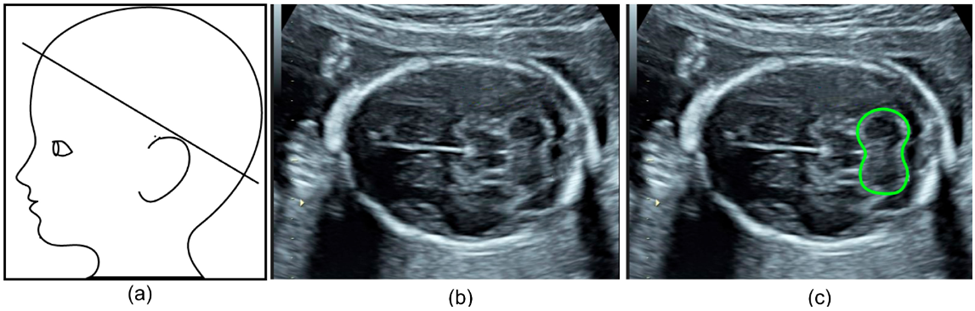

Specifically, one group aimed to automate the detection and segmentation of the fetal cerebellum. The cerebellum is a brain region comprised of a dense network of neurons involved in motor coordination and motion calibration. This structure is also used as a benchmark for brain development during fetal ultrasound scans as structural changes report neurodevelopmental stages and might report neurodevelopmental outcomes. The authors developed a deep learning algorithm to automatically segment the cerebellum in two-dimensional ultrasound images (Figure 4b). Their model was highly accurate with an 86% overlap compared to manual annotation, making it a reliable and efficient alternative.